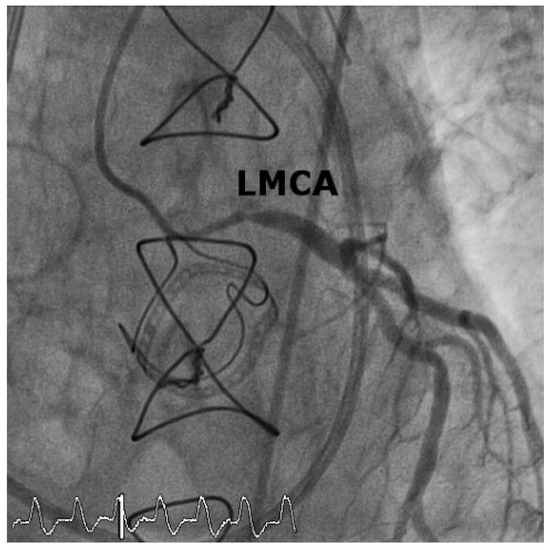

Iatrogenic Left Main Stem Stenosis After Surgical Aortic Valve Replacement

by Jens Robert, David Tüller and Stephan Windecker

Cardiovasc. Med. 2011, 14(3), 101; https://doi.org/10.4414/cvm.2011.01578 - 23 Mar 2011

Surgical aortic valve replacement (SAVR) represents the gold standard in the treatment of symptomatic severe aortic valve stenosis as reflected by the class I indication assigned in the ACC/AHA and ESC guidelines. SAVR effectively relieves symptoms, improves quality of life as well as [...] Read more.

Surgical aortic valve replacement (SAVR) represents the gold standard in the treatment of symptomatic severe aortic valve stenosis as reflected by the class I indication assigned in the ACC/AHA and ESC guidelines. SAVR effectively relieves symptoms, improves quality of life as well as prognosis of affected patients. As with any therapeutic intervention, SAVR is associated with some short and long term adverse events including death, stroke, myocardial infarction, renal failure, bleeding, as well as structural and non-structural valve deterioration. We present two cases of iatrogenic left main stemstenosis within less than one year after SAVR, describe the management and discuss the literature. Full article